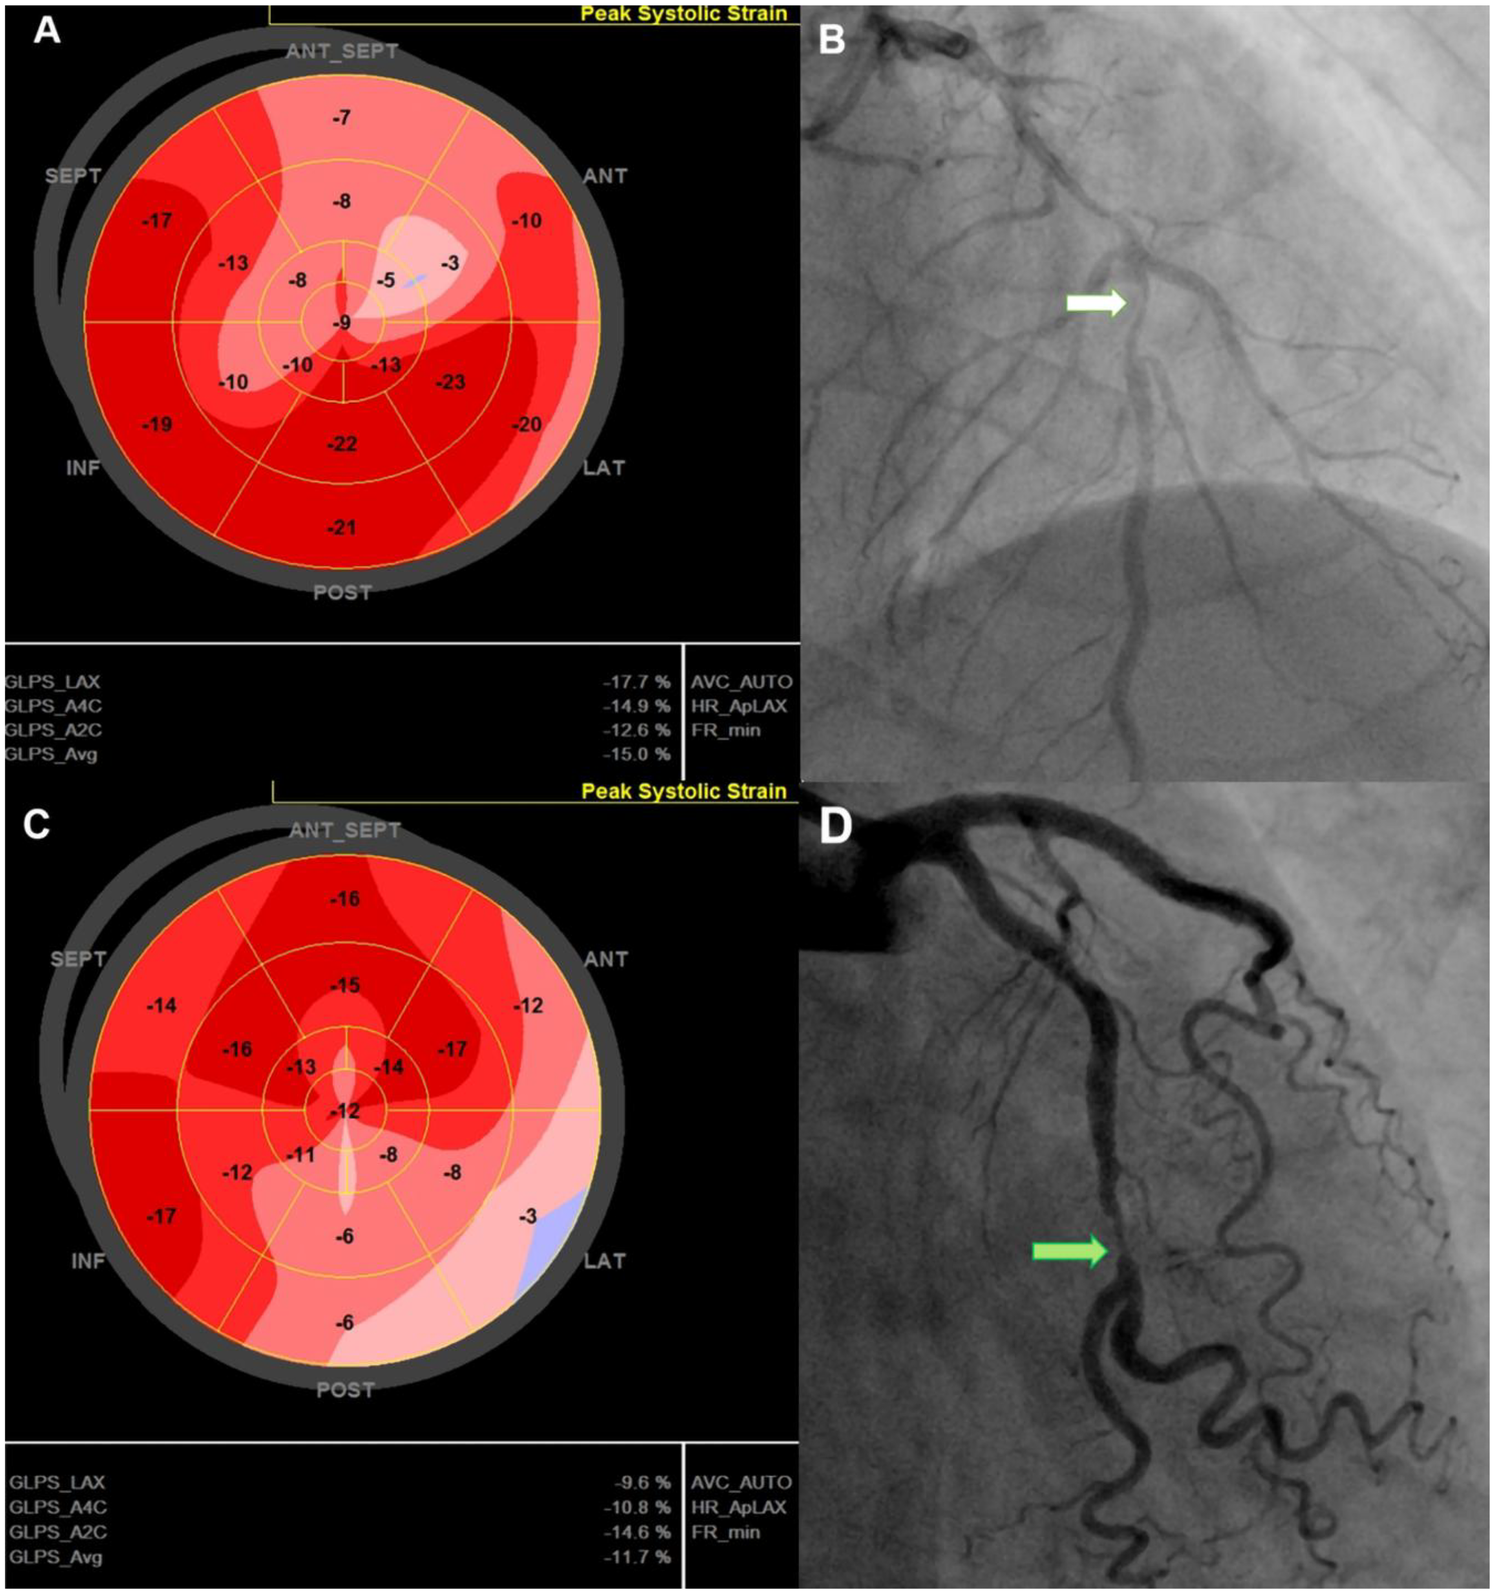

Findings on coronary angiography were recorded (Figure 1), including the culprit lesion, the number of diseased vessels, and lesion complexity as assessed by the SYNTAX (SYNergy between PCI with TAXUS™ and Cardiac Surgery) score. Additional biochemical workup included creatinine, peak high-sensitivity troponin T (hs-Troponin T), N-terminal pro-B-type natriuretic peptide (NT-proBNP) and complete blood count during the hospital stay.

The left ventricle was divided into 17 segments, covering the entire myocardium (25). Strain values were calculated by averaging the mean value in each segment (Figure 1). GCS and GRS were assessed from parasternal short-axis views at basal, mid, and apical levels. The short-axis region of interest was subdivided into six segments. The endocardium and epicardium were tracked manually. The anterior insertion point of the right ventricular free wall served as an anatomical landmark. The GCS and GRS were determined by averaging segmental-level measurements obtained from the same frames. All assessments were performed over three consecutive cardiac cycles and the results were averaged.

Representative cases illustrating GLS characteristics in post-PCI NSTE-ACS patients. 74-year-old man with a GLS of −15%, reduced longitudinal strain in the anterior septal region (A), EF of 51%, 90% stenosis of the LAD (white arrow)—(B), and no MACE during follow-up. 67-year-old man with a GLS of −11.7% with reduced strain in the lateral and posterior regions (C), LVEF of 52%, and 90% stenosis of the LCx (green arrow) (D); admitted for acute heart failure within 12-month follow up. GLS, Global Longitudinal Strain; LAD, left anterior descending (coronary artery); LCx, left circumflex (coronary artery); LVEF, left ventricular ejection fraction; MACE, major adverse cardiovascular events; PCI, percutaneous coronary intervention.